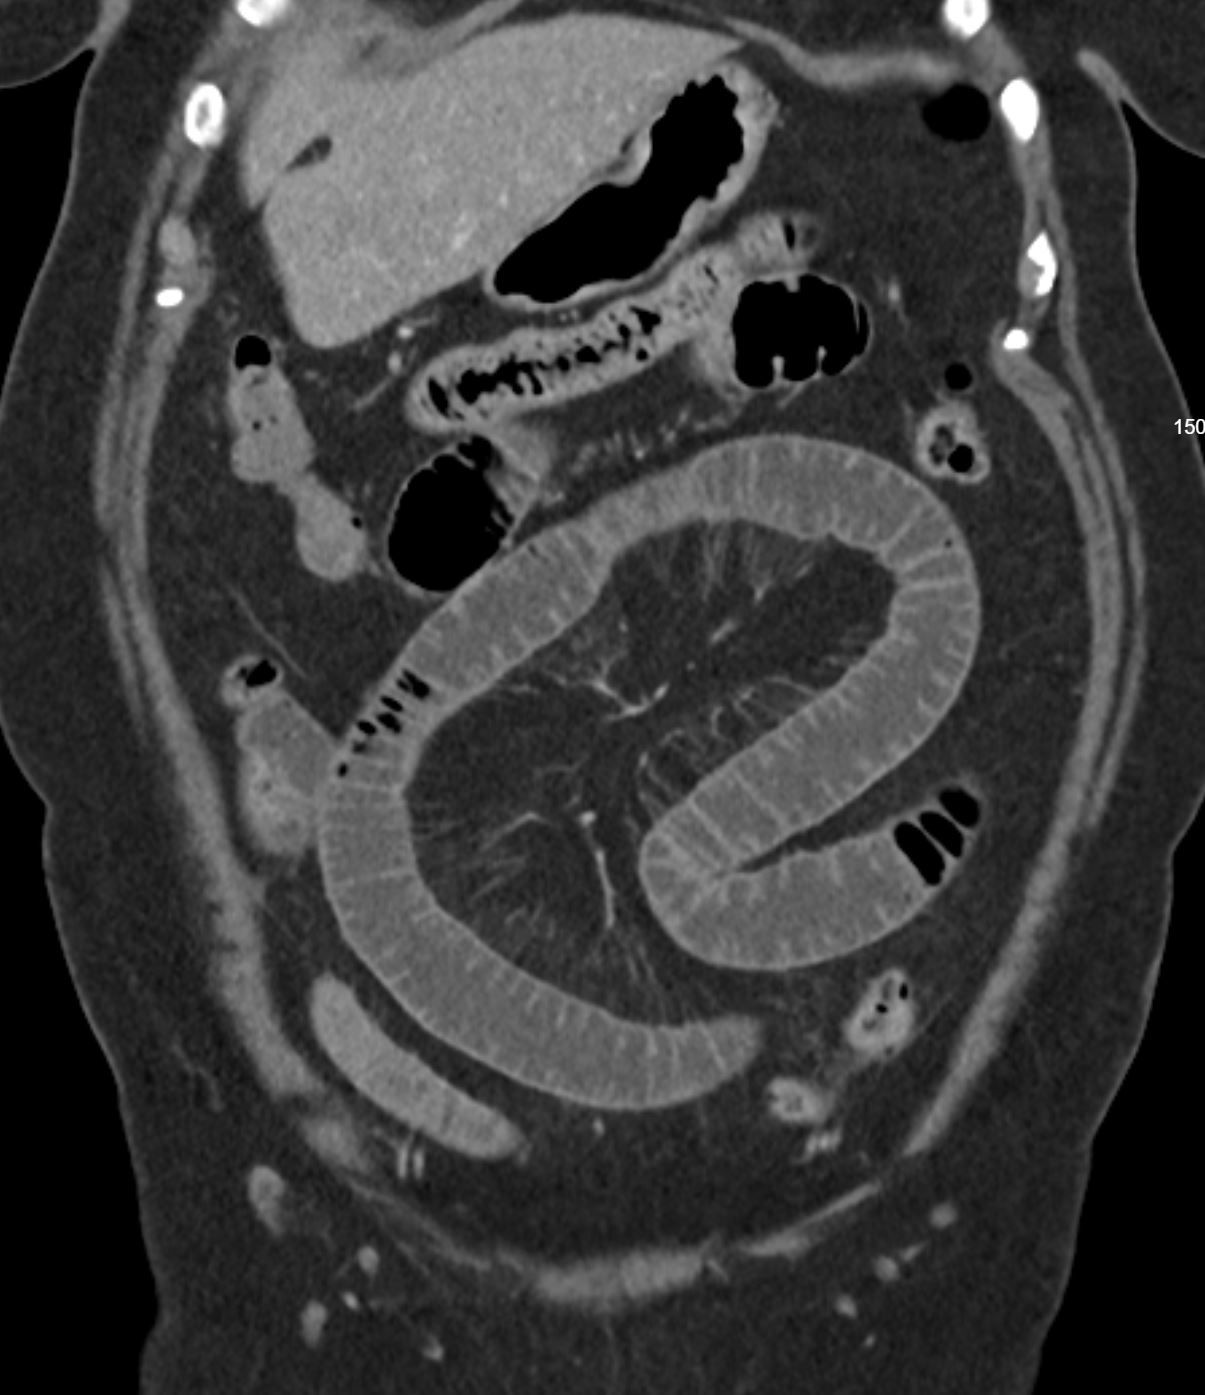

Image IQ Quiz: 59-Year-Old Patient Presents with Abdominal Pain

What is your diagnosis for this 59-year-old patient who presents with abdominal pain?

What is your diagnosis?